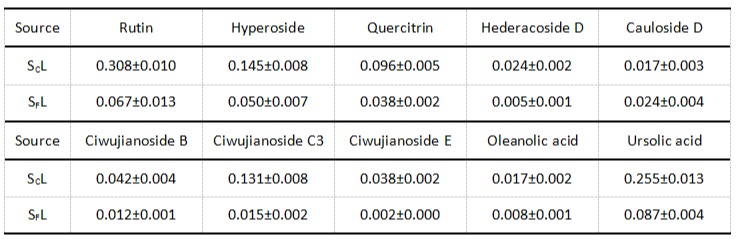

进一步通过基于多变量统计分析的非靶向代谢组学技术,团队还识别出SCL及SFL标志性的20种及7种成分。其中,齐墩果烷型三萜皂苷(如Ciwujianoside C1、C3、D2、E,Saniculoside N等)可作为SCL的鉴别标志,而羽扇豆烷型三萜皂苷(如(1-deoxy-chiisanoside和24-hydroxy-chiisanoside)则适用于SFL的快速鉴定。为精确量化关键成分,研究还建立了HPLC-ELSD方法,实现了芦丁、槲皮素等10种成分的同时测定(表1)。

表1 SCL及SFL中10种化学成分的含量